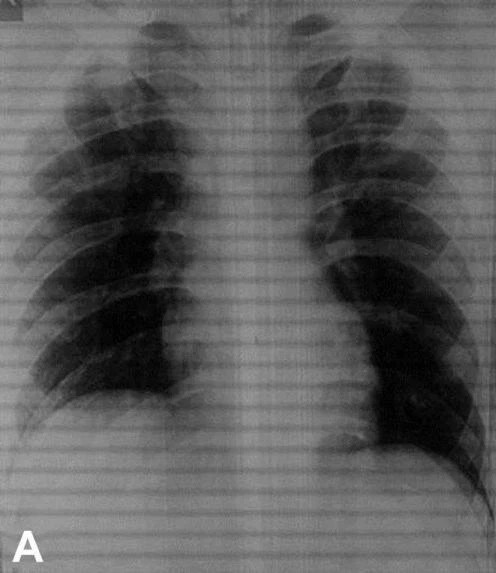

Hindistan’da 26 yaşında ismi açıklanmayan bir adam, banyoda kayarak duş başlığının üzerine düştüğünü söyleyerek hastaneye gitti. Doktorların yaptığı incelemeler sonucunda, duş başlığının adamın rektumundan 15 santimetre kadar içeri girdiği tespit edildi.

Başarılı bir operasyon geçirdiği açıklanan adamın sağlık durumunun iyi olduğu ifade edildi.

Konuyla ilgili açıklamalarda bulunan doktorlar, adamın hikayesinin inandırıcı gelmediği ve ‘muhtemelen’ yaşanan olayın ‘kaza olmadığı’ yönünde görüş belirtti.